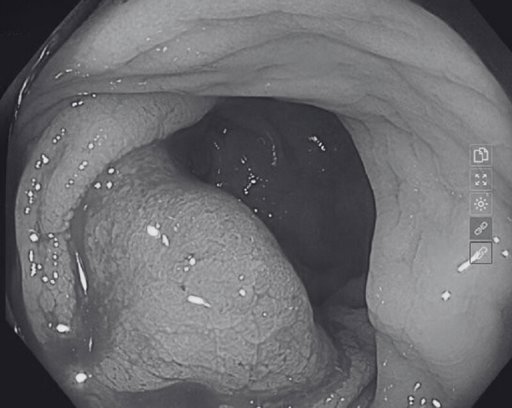

Kết quả xét nghiệm của chị H., dương tính với 12 type HPV nguy cơ cao. Xét nghiệm tế bào Thinprep có kết quả ASGUS (Tế bào tuyến không điển hình ý nghĩa chưa xác định). Thực hiện soi cổ tử cung nhiều cửa tuyến, tăng sinh mạch mép dưới CTC. Test acid acetic có vết trắng điển hình vị trí 12h-1h cổ tử cung.

Sinh thiết cổ tử cung cho kết quả Carcinoma vảy tại chỗ (CIS)

Đặc biệt, dựa vào tiêu chuẩn “vàng” - xét nghiệm giải phẫu bệnh cho kết quả Carcinoma (ung thư biểu mô) vảy tại chỗ (CIS). Sau đó, bệnh nhân được chuyển đến Bệnh viện Phụ sản TW điều trị gồm cắt tử cung hoàn toàn và hai phần phụ.